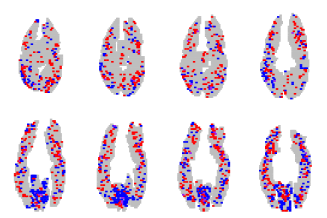

We trained 3 classifiers using 4-fold cross validation to select the regularization parameter, considering all available voxels without preselection. We group regions of voxels and considered overlapping groups “shifted” by 2 voxels in the first 2 dimensions.222The irregular group size compensates for voxels being larger and scanner coverage being smaller in the z-dimension (only 8 slices relative to 64 in the x- and y-dimensions). Figure 3 shows the individual error rates across the 6 subjects for the three methods. Across subjects, SOSlasso had a significantly lower cross-validation error rate (27.47 %) than individual lasso (33.3 %; within-subjects t(5) = 4.8; p = 0.004 two-tailed), showing that the method can exploit anatomical similarity across subjects to learn a better classifier for each. SOSlasso also showed significantly lower error rates than glasso (31.1 %; t(5) = 2.92; p 0.03 two-tailed), suggesting that the signal is sparse within selected regions and variable across subjects.

Figure 3 presents a sample of the the sparsity patterns obtained from the different methods, aggregated over all subjects. Red points indicate voxels that contributed positively to picture classification in at least one subject, but never to sentences; Blue points have the opposite interpretation. Purple points indicate voxels that contributed positively to picture and sentence classification in different subjects. The remaining slices for the SOSlasso are shown in Figure 3.

There are three things to note from Figure 3. First, the Glasso solution is fairly dense, with many voxels signaling both picture and sentence across subjects. We believe this “purple haze” demonstrates why Glasso is ill-suited for fMRI analysis: a voxel selected for one subject must also be selected for all others. This approach will not succeed if, as is likely, there exists no direct voxel-to-voxel correspondence or if the neural code is variable across subjects. Second, the lasso solution is less sparse than the SOSlasso because it allows any task-correlated voxel to be selected. It leads to a higher cross-validation error, indicating that the ungrouped voxels are inferior predictors (Figure 3). Third, the SOSlasso not only yields a sparse solution, but also clustered. To assess how well these clusters align with the anatomical regions thought a-priori to be involved in sentence and picture representation, we calculated the proportion of selected voxels falling within the 7 ROIs identified by [20] as relevant to the classification task (Table 2). For SOSlasso an average of 70% of identified voxels fell within these ROIs, significantly more than for lasso or Glasso.

We trained a classifier using 4-fold cross validation on the star plus dataset [20]. Figure 4 shows the discovered sparsity patterns in their entirety for the three methods considered, projected into a brain space that is the union over all size subjects; anatomical data was not available. In each slice, we aggregate the data for all the 6 subjects. Red points indicate voxels that contributed positively to picture classification in at least one subject, but never to sentences; Blue points have the opposite interpretation. Purple points indicate voxels that contributed positively to picture and sentence classification in different subjects.

The following observations are to be noted from Figure 4. The lasso solution (Figure 4(a)) results in a highly distributed sparsity pattern across individuals. This stems from the fact that the method does not explicitly take into account the similarities across brains of individuals, and hence does not look to “tie” the patterns together. Since the alignment is not perfect across brains, the 6 resulting patterns when aggregated result in a distributed pattern, and the largest error among the methods tested.

The Glasso (Figure 4(b)) for multitask learning ties a single voxel across 6 subjects into a single group. If a particular group is active, then all the coefficients in the group are active. Hence, if a particular voxel in a particular subject is selected, then the same location in another subject will also be selected. This forced selection of voxels results in many coefficients that are almost but not exactly 0, and random signs as can be seen from the histogram of the selected voxels in Figure 4(c).

The lasso with Sparse Overlapping Sets (Figure 4(d)) overcomes the drawback of the Glasso by not forcing all the voxels at a particular location to be active. Also, since we consider groups here, we also tend to group voxels that are spatially clustered. This results is selecting voxels in a subject that are “close-by” (in a spatial sense) to voxels in other subjects. The result is a more clustered sparsity pattern compared to the lasso, and very few ambiguous voxels compared to the Glasso.